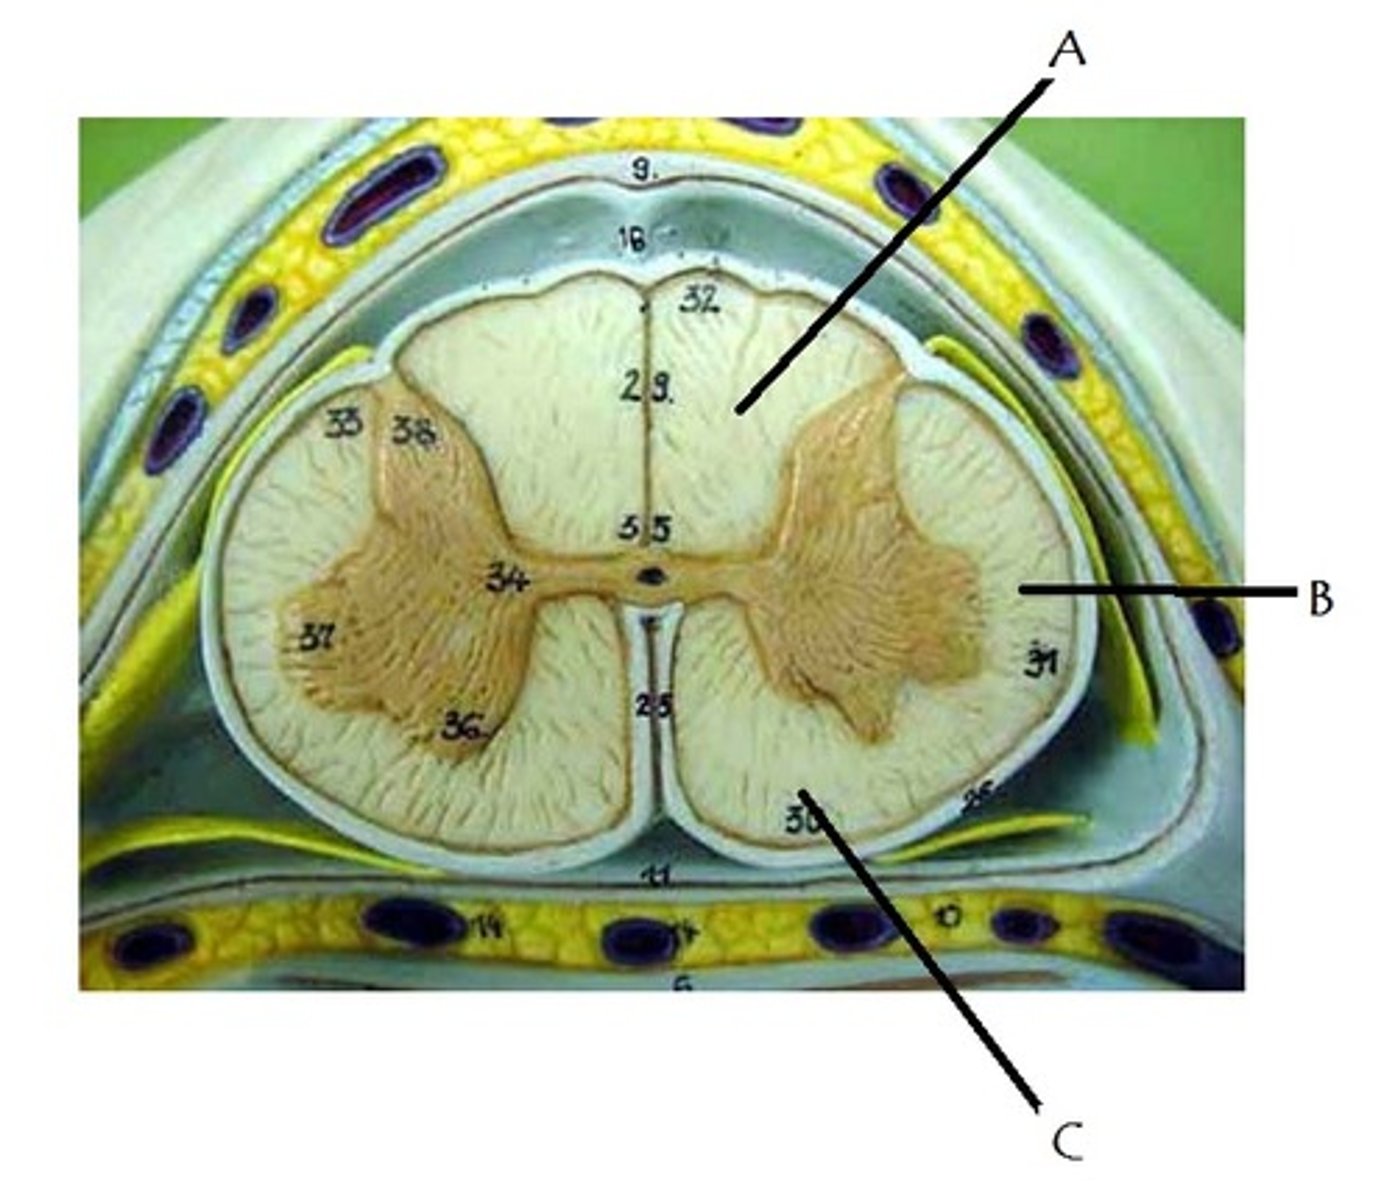

posterior white column

A

anterior white column

C

lateral white column

B

posterior gray horn

anterior gray horn

lateral gray horn

gray commissure

Part of grey matter connecting the two halves of the grey matter in spinal cord

central canal

Hole in the center

Name this passageway